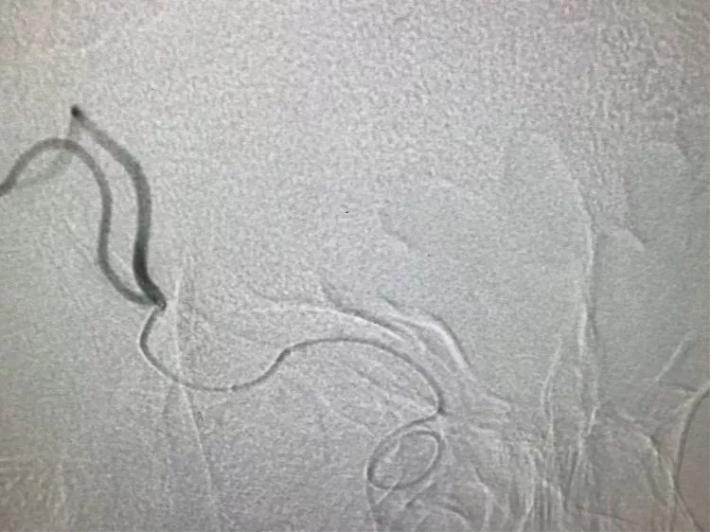

桥接动脉取栓,造影显示:基底动脉闭塞。

微导管进入基底动脉尖部,显示进入真腔。

置入支架,见基底动脉有血流。

取出支架,血管闭塞。

第二次上微导管进入真腔。

置入支架,基底动脉有血流。

取出支架,血管未开通。

第三次上微导管。

支架打开取栓。

见基底动脉血流恢复,左侧大脑后动脉血流欠佳。